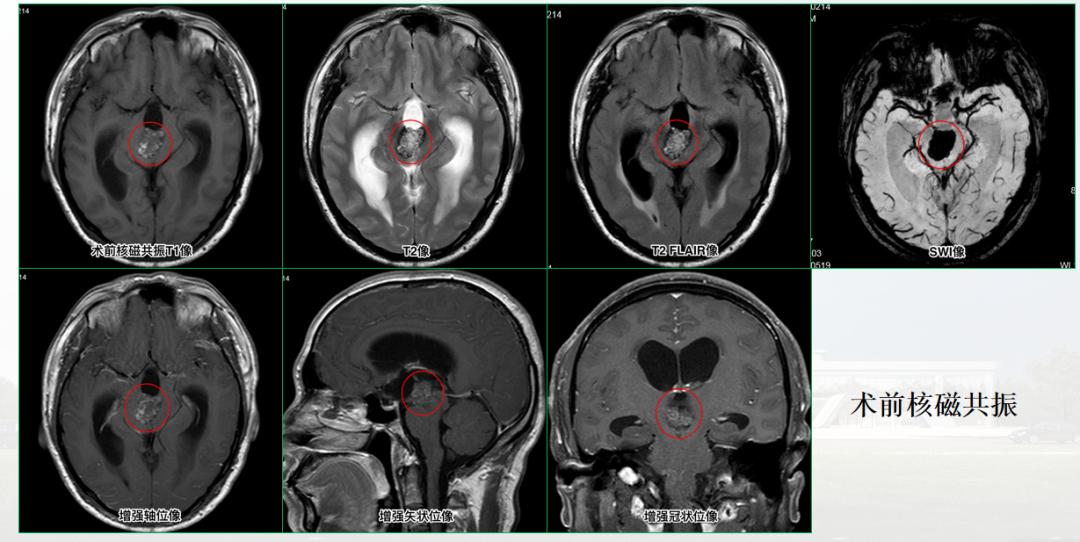

直到5月初,病情加重,头痛更为严重,双眼也出现视物模糊的症状,才到当地医院就诊,检查结果却出乎他的意料,影像学检查显示:三脑室内占位性病变,双侧侧脑室扩大,伴有脑积水等症状。

入院后,综合李先生的病史、症状、相关检查,张院长考虑可能性最大的是三脑室海绵状血管瘤。

张院长介绍:“颅内海绵状血管瘤可发生在中枢神经系统的任何部位,但最常发生于侧脑室,生长在第三脑室的海绵状血管瘤相当罕见,第三脑室位于人脑中央,位置深在,周围重要结构众多,要够到脑深部的肿瘤,并尽可能的全切,最大限度的保留神经功能,对手术设备和手术医生的技术要求极高,另外,第三脑室肿瘤周围脑组织缺乏,肿瘤生长阻力较低,脑室内海绵状血管瘤生长速度较快,可形成巨型畸形,三脑室海绵状血管瘤是脑室手术中的难点。从检查结果看,患者的肿瘤钙化明显,大小约3X2X2cm,占满三脑室,海绵状血管瘤的血管结构不同于正常血管,没有内皮组织,非常脆弱,稍有不慎将造成大出血,或出现严重神经功能障碍,手术的风险和难度可想而知。”

病理标本检测,确诊为三脑室海绵状血管瘤,这也证实了张院长的诊断。